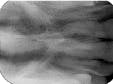

The bisecting-angle technique creates specific errors in vertical angulation, giving shortened images (see Radiograph 2 as an example of foreshortening) or lengthened images (see Radiograph 3 as an example of elongation). Substantially shortened images occur because there is too much vertical angulation. This causes distortion in the reproduction of the actual size of the tooth. The solution requires a decrease of the vertical angulation by at least 10 degrees.